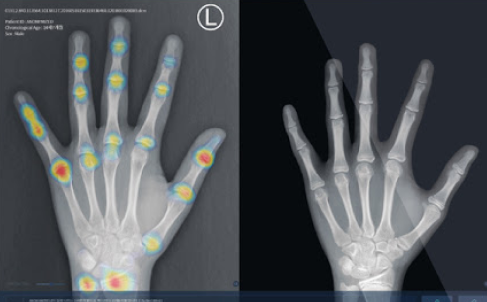

성장판검사